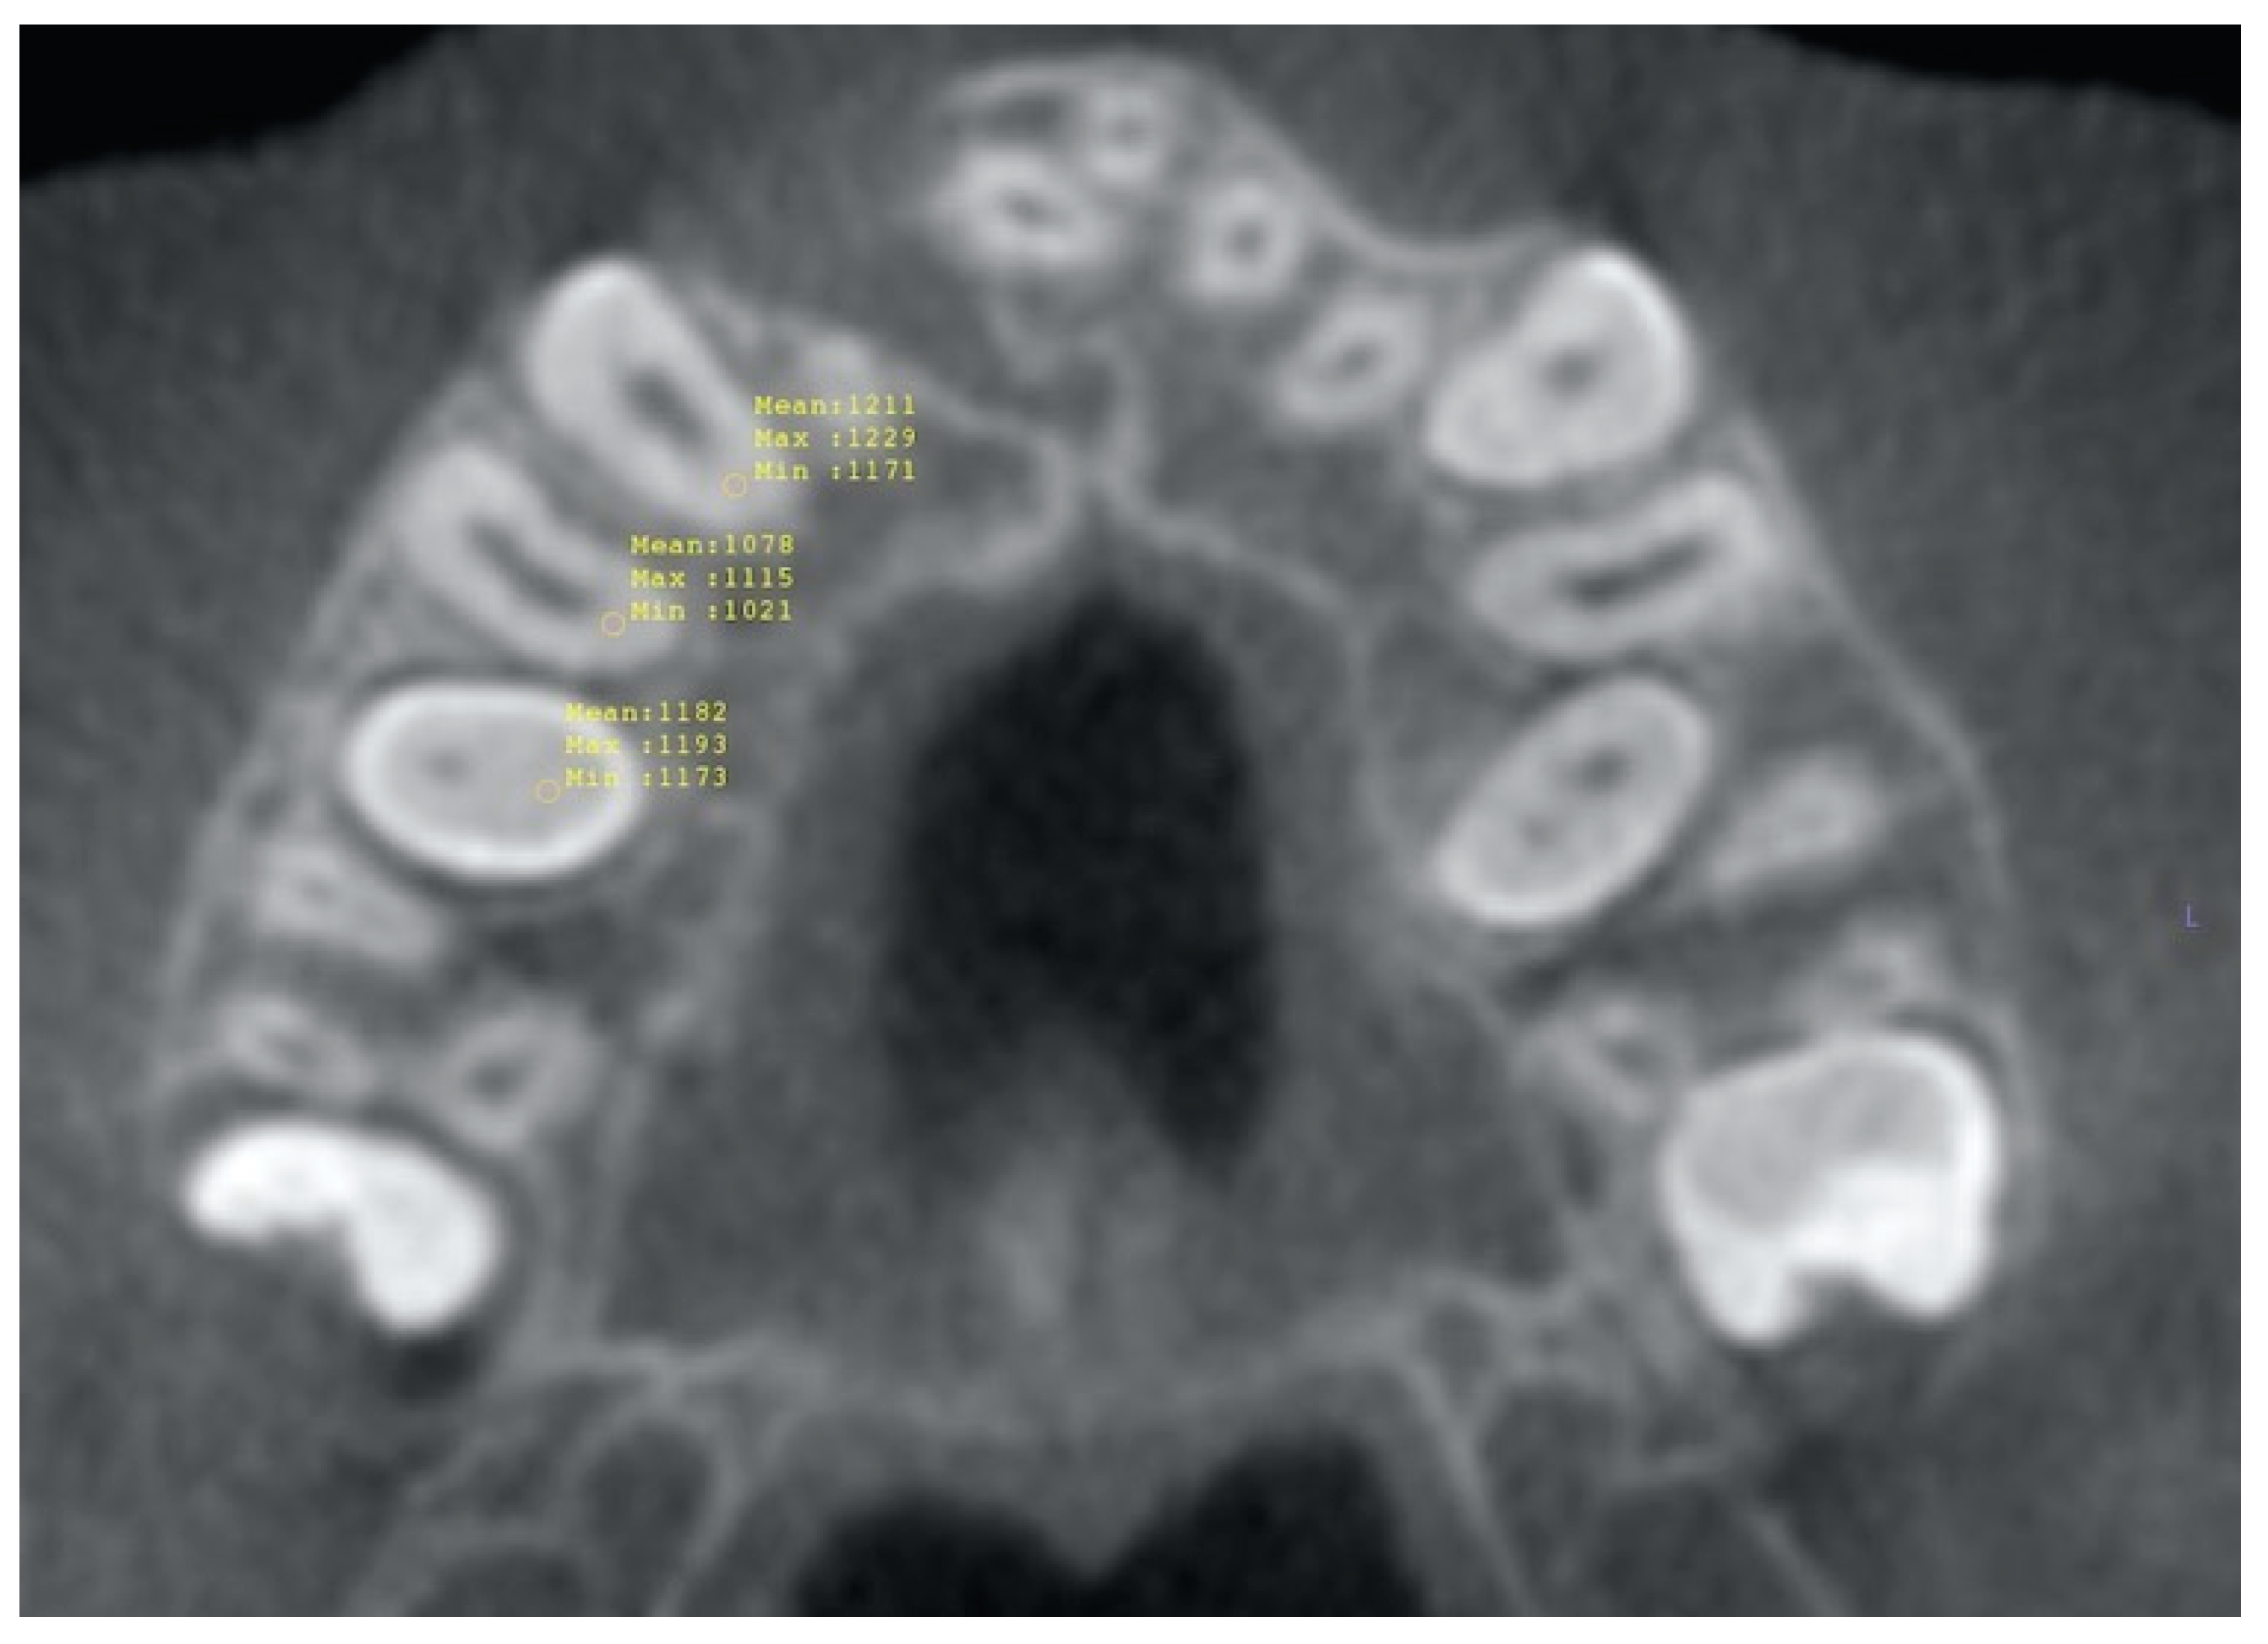

2.1. Volumetric Analysis